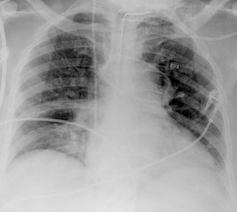

Se recurre a esta técnica de imagen porque, debido a la afectación primaria del sistema respiratorio, la infección por SARS-CoV-2 deja evidencias radiológicas de neumonía visibles bajo los rayos X. Concretamente, la neumonía asociada a la covid-19 produce sombras en los pulmones conocidas como opacidad de vidrio esmerilado. Estas opacidades suelen aparecer con una distribución periférica o posterior, principalmente en los lóbulos inferiores y con menos frecuencia en el lóbulo medio derecho.

En los dos primeros días de la infección, el 50% de los pacientes de covid-19 ya muestra lesiones pulmonares parenquimatosas, superando el 90% entre los 3 y 5 días. Lo sorprendente es que esto ocurre incluso en pacientes asintomáticos. Por ello, complementar la RT-PCR con una radiografía de tórax mejora la sensibilidad en el diagnóstico, reduciendo significativamente el número de falsos negativos. Es importante porque los falsos negativos son precisamente el talón de Aquiles de la prueba RT-PCR, cuya sensibilidad oscila entre el 70-90%. Otra ventaja importante es que la radiografía está lista en cuestión de minutos.

La única pega al uso de esta técnica es que su despliegue masivo tiene un significativo cuello de botella: la necesidad de radiólogos expertos para interpretar y analizar las imágenes. Adicionalmente, el análisis individual de la radiografía de tórax, tal y como lo conocemos, también adolece de una baja sensibilidad, lo que sugiere la necesidad de herramientas complementarias de análisis computerizado.